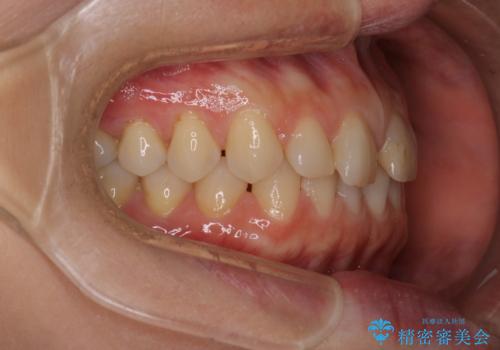

【審美装置】すきっ歯をワイヤー装置で治したい

- 前歯のすきっ歯が気になるということで来院されました。今回は抜歯はしないためワイヤー矯正かインビザライン矯正のどちらでも治療可能でしたが、患者さまのご希望により表のワイヤー装置にて治療をおこないました。

前歯に隙間がいくつかあったため、今回は上下でゴムかけを行いスペースを埋めるための力をかけて閉じました。もう少し早く終了する予定でしたが、ブラッシング不良による歯肉腫脹があり、一部スペースクローズに時間がかかりました。